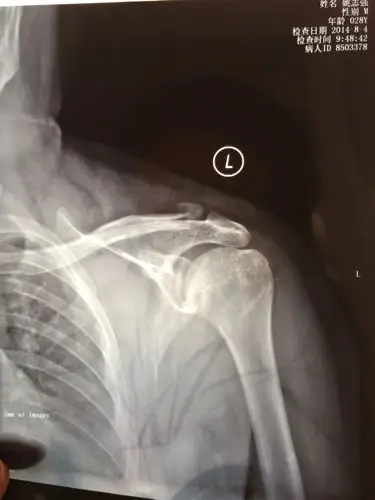

我骑车不慎将左侧肩膀摔伤,去医院拍片诊断为左侧锁骨肩峰端骨折,10